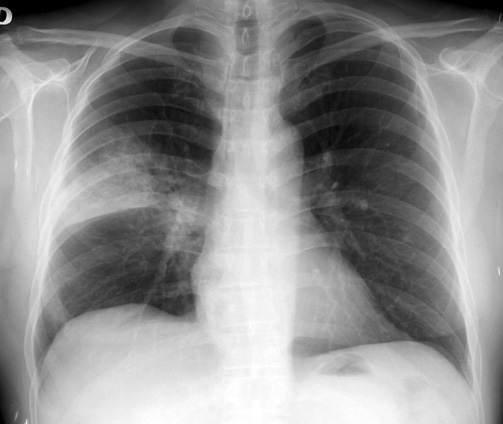

EClinicalMedicine, 1 de enero de 2019 La vacuna neumocócica polisacárida 23-valente ofrece protección moderada a corto plazo contra la enfermedad neumocócica invasiva (ENI) en adultos mayores. Los serotipos PPV23 comprenden una proporción cada vez mayor de casos de ENI en adultos mayores debido a la sustitución de serotipos después del uso rutinario de vacunas conjugadas neumocócicas en niños.

La vacuna redujo en un 33% las neumonías por serotipos incluidos en la vacuna, y en un 27% el total de neumonías por neumococo en esta población. Lancet Infectious Diseases, 23 de enero de 2017